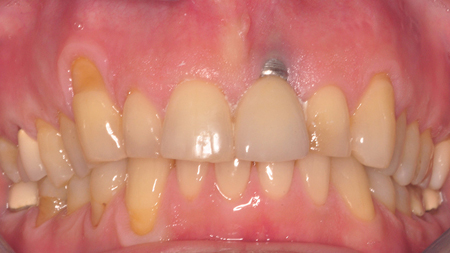

Minimally Invasive, Inter-Disciplinary Management for Cosmetic Rehabilitation in a High Smile Line Patient: A Case Report

Said-Picture6 alternate text for this image

Introduction: The purpose of this case report is to illustrate the potential of utilizing digital technology to minimize surgical invasion and increase precision in management of compromised sites in the esthetic zone. Article In modern-day implant dentistry, the ability to achieve a harmonious integration of the implant restoration is no longer optional but to a … Read more